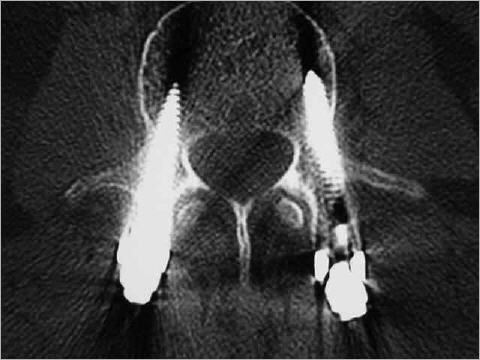

Hier wurde ein ganzer Wirbel entfernt und durch ein Implantat ersetzt. Ein solcher Eingriff ist bei Tumorbefall, komplizierten Wirbelbrüchen und Knocheneiterungen notwendig; zum Beispiel bei Tuberkulose.

Knochenschrauben im Wirbel: Mit Computernavigation wird die Stabilisierung durchgeführt und gibt dem Patienten maximale Sicherheit.